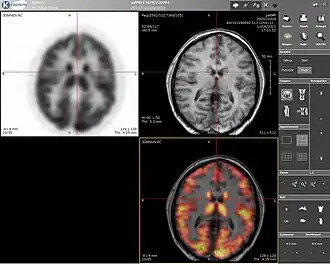

Computer screenshot showing a PET image (upper left), an MRI image (upper right), and the combined PET–MRI image where PET data is overlaid over the MRI data (lower right)